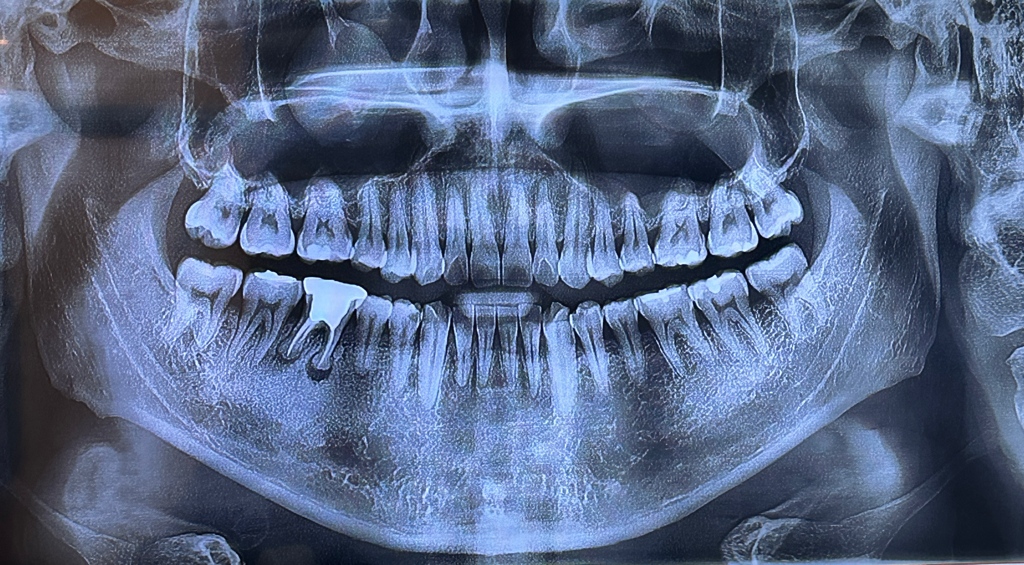

무조건 뼈이식이 필요할까요? 임플란트 고민입니다

오른쪽 6번치아 때문에

해당 사진만으로는 뼈이식 가능성을 함부로 말씀드리기 어렵습니다. 파노라마 사진은 3차원을 2차원으로 옮겨 놓았기 때문에 골의 정확한 모양이나 패턴을 보기 힘듭니다. 현재 사진으로 보았을 때는 뼈이식 가능성을 열어두고 수술하는 것이 맞습니다.

일반적으로 골이식은 임플란트를 하고 난 다음에 빈 공간이 있을 때 하게 되는데 발치를 하고 바로 임플란트를 하게 된다면 발치한 부위에 빈 공간이 있어서 골이식을 해야 하는 경우가 많습니다.

하지만 발치를 한 후에 충분한 시간이 지나서 잇몸뼈가 차오른 다음에 임플란트를 한다면 식이 필요하지 않을 수도 있습니다.

저정도 상태라면 발치를 하고 조금 기다렷다가 뼈이식을 하지 않고 임플란트를 식립하셔도 될것같습니다.